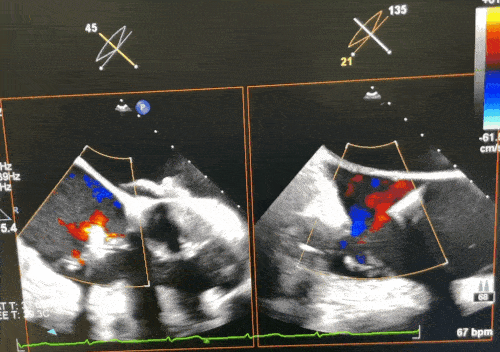

术前超声2